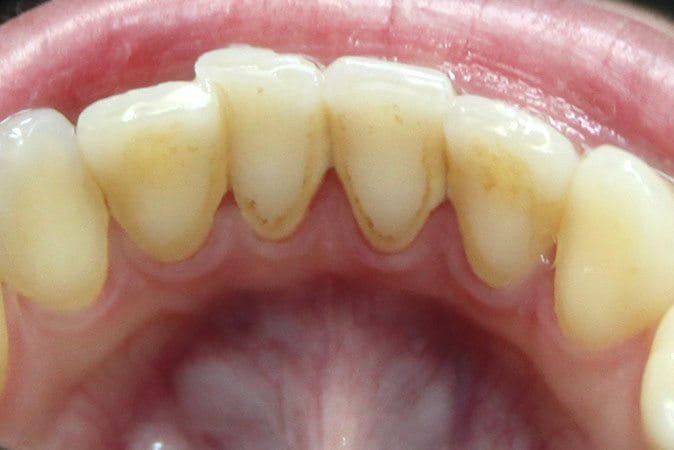

Tartar, also called dental calculus, is a yellow or brown colored deposit that forms when plaque hardens on your teeth and contributes to their decay.

Plaque is riddled with harmful bacteria that damage tooth enamel and cause cavities. If you don’t remove the plaque from your teeth, it hardens into tartar. Tartar consists mostly of mineralized dead bacteria and proteins.

Not only does tartar damage the teeth and gums, it also poses a cosmetic problem. Because tartar is more porous, it absorbs stains easily. If you drink coffee or tea, or if you smoke, it is especially important to know how to remove tartar from your teeth without going to a dentist, and how to prevent it from forming again.